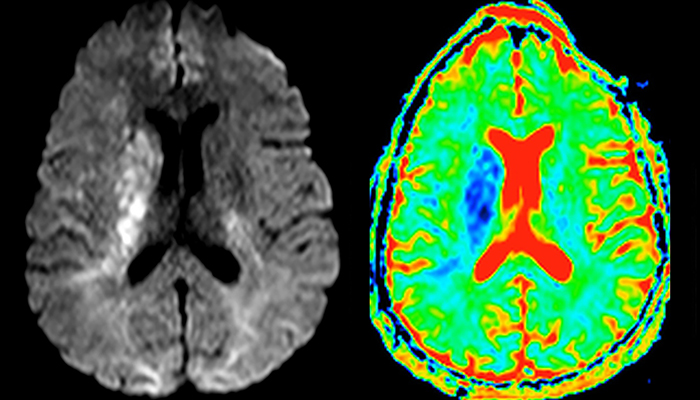

„In Frankreich werden Schlaganfälle in der Regel per MRT und nicht per CT untersucht, auch bei der Notfallbehandlung.“ „In Frankreich erfolgt die Bildgebung bei Schlaganfällen in der Regel per MRT, nicht per CT, auch bei der Notfallbehandlung. Das liegt daran, dass wir mit der MRT eine Ischämie in der akuten Phase direkt darstellen, aber auch Differenzialdiagnosen wie MS und Hämatom ausschließen können. Außerdem ist es uns möglich, die intrakraniellen und extrakraniellen Gefäße im Laufe derselben Untersuchung zu beurteilen“, sagt Dr. Savatovsky.

Die erste Herausforderung bei der Magnetresonanztomographie betrifft die Geschwindigkeit. Die Patienten werden in der Regel aus einem Rettungswagen in den MRT-Vorbereitungsraum gebracht und die Einrichtung erfolgt an einem separaten Platz außerhalb des Technikraums. „Der venöse Zugang wird während der neurologischen Untersuchung gelegt. Wenn es der zeitliche Abstand von den ersten Symptomen erlaubt, dass der Patient eine Thrombolyse erhält, führen wir eine sehr schnelle Untersuchung durch, die üblicherweise etwa 11 Minuten dauert, einschließlich der Pre-Scans. Bei einem transienten ischämischen Schlaganfall erfolgt im Regelfall zusätzlich eine ASL-Perfusionsbildgebung, weil bei manchen Symptomen mit negativer Diffusion ASL eine vaskuläre Ursache anzeigt.“

„Ingenia bietet eine große Flexibilität bei der Parametereinstellung, d.h., wir können eine Sequenz beliebig abstimmen“, erklärt Dr. Savatovsky. „Bei einer Schlaganfalluntersuchung nutzen wir zum Beispiel eine FLAIR-Sequenz von etwa zwei Minuten anstelle der vierminütigen Sequenz, die wir bei MS verwenden. Die Diffusionsbildgebung dauert 30 Sekunden, der T2*-gewichtete Scan ebenfalls 30 Sekunden und die Scan-Dauer bei der Angiographie beträgt weniger als eine Minute. Ingenia ist in dieser Situation ein großartiger Scanner. Auch bei diesen schnellen Sequenzen erzielen wir hochwertige Bilder mit einem guten Signal-Rausch-Verhältnis. Wenn wir anhand der ersten Sequenz feststellen, dass es sich nicht um einen ischämischen Schlaganfall, sondern um einen hämorrhagischen Schlaganfall handelt, können wir zu einer zeitaufgelösten Angiographie wechseln, um nach vaskulären Malformationen und einer Venenthrombose zu suchen.“

„Jede Klinik arbeitet anders, aber für mich umfasst das ideale Schlaganfallprotokoll die diffusionsgewichtete Bildgebung, die FLAIR- und die schnelle suszeptibilitätsgewichtete Bildgebung“, sagt Dr. Savatovsky. „Unsere schnelle suszeptibilitätsgewichtete Bildgebung dauert nur 50 Sekunden, sie ist also genauso schnell wie die T2*-gewichtete Bildgebung. Damit werden Blutungen, aber auch Koagulationen dargestellt. Wir führen zusätzlich eine 3D-MR-Angiographie durch, die Informationen über zervikale und zerebrale Gefäße liefert. Wenn die Patienten keine sofortige Behandlung benötigen oder wenn zusätzliche Informationen erforderlich sind, um über die Therapie zu entscheiden, nehmen wir außerdem eine Perfusionsbildgebung und eine T1-gewichtete Postkontrastbildgebung vor.“